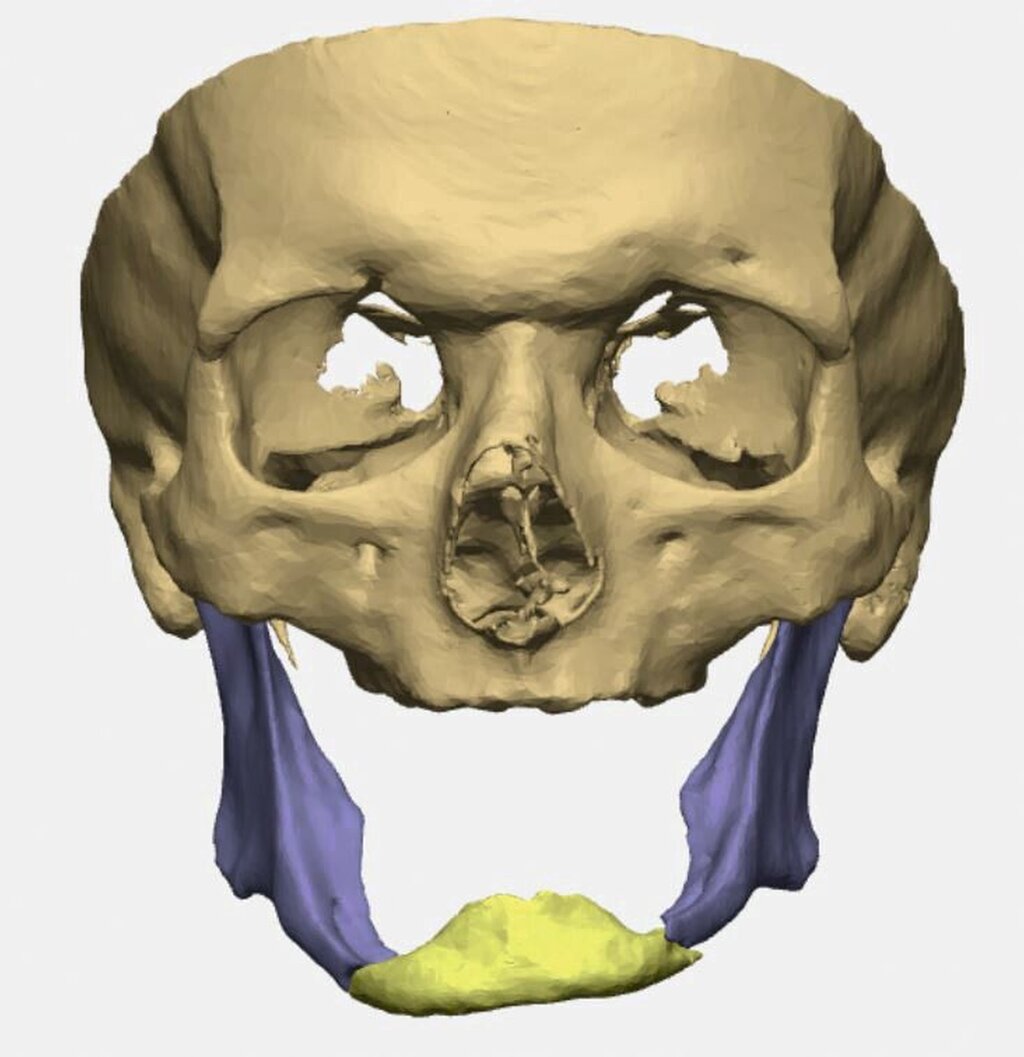

Bei zahnlosem Ober- und Unterkiefer erfolgte die virtuelle Repositionierung des frakturierten Unterkiefers (Abbildung 2a). Mittels CAD/CAM-Verfahren wurde eine stabile Rekonstruktionsplatte aus Titan (patientenspezifisches Implantat; PSI) geplant und hergestellt. Dabei sollte die Position des PSIs im Bereich des Unterkieferkorpus weit kaudal an der Basis sein, so dass später bei der Anpassung einer neuen Unterkieferprothese keine Interferenzen auftreten (Abbildung 2b).

Gleichzeitig konnte durch eine optimierte Bohrlochposition der Nervus alveolaris inferior geschont werden, eine Neurolyse brauchte nicht geplant zu werden. Außerdem wurden an die Zielreposition angepasste Bohrschablonen (drilling guides) hergestellt, die ein Vorbohren der späteren Schraubenlöcher in der exakten Zielposition ermöglichen (Abbildung 2c). In Kombination mit dem PSI sollte so eine Auto-Reposition des Unterkiefers durch die vorgegebenen Bohrlöcher erfolgen.